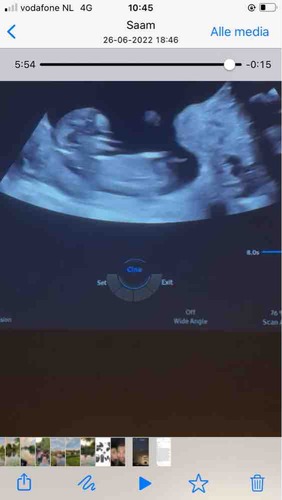

Jammergenoeg kan ik van de laatste echo ook de nub niet goed zien. En weet ook niet zeker of het de blaas is wat ik zie. Als je een filmpje hebt zou het mooi zijn als je een paar foto's maakt van stilstaand beeld. Maakt niet uit of het er meerdere zijn en of je toch wat van het beentje ziet zoals bij de vorige echo. Want soms lukt het met bewerken alles toch scherper en duidelijker te krijgen. Filmpjes kun je volgens mij nog steeds niet plaatsen in dit forum. Op het moment begin ik een beetje te neigen naar dat het een jongen in wording is. Maar moet daar toch wat meer dingen voor zien voor ik een gok neem.

Bedankt voor de uitgebreide uitleg.👌🏻 Ik ben 13+6.

Moet wel zeggen dat ik wel wat meer had verwacht met dat termijn. Vaak zie je dan al echt pipi en balletjes omhoog staan. Maar kan ook liggen aan hoe ze de echo gemaakt hebben. Bij een meisje met dit termijn moest het zowiezo plat zijn. Dus denk dat ze expres de echo wat minder duidelijk(donkerder) hebben gehouden bij de nub heb ik wel wat vaker gemerkt.

Maar door alle duideljke dingen gok ik toch echt jongen. Laat je het nog even weten als je het weet?